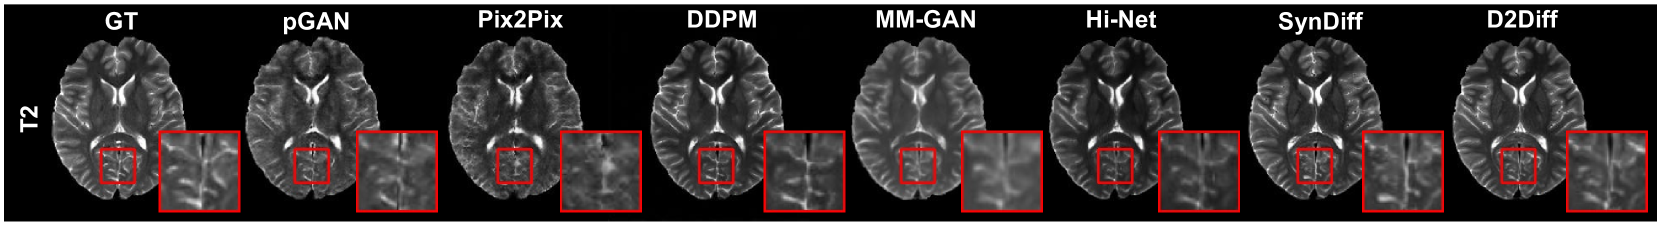

The qualitative performance of D2Diff is illustrated in Fig. 2 and 3 for both healthy and BraTS synthetic results. For healthy subjects, D2Diff better preserves anatomical structures, offering superior contrast details compared to other methods. In tumour datasets, it improves lesion synthesis, particularly in challenging tasks like T1CE, where other methods struggle with contrast enhancements. It produces sharper tumour boundaries that closely resemble ground truths. Additionally, the quantitative evaluation in Table 1 for PSNR, SSIM, MAE[18] confirms D2Diff’s superiority, outperforming all methods across tasks.

Figure 2: Visualization of synthetic MRI results on healthy dataset.

Refer to caption

Figure 3: Visualization of synthetic MRI results on BraTS dataset.